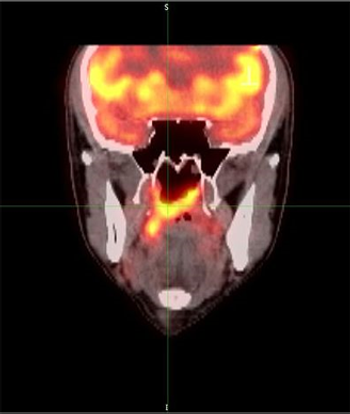

Data from a pooled analysis show that PET-CT provided better response assessment than did CT and predicted inferior survival in follicular lymphoma patients.